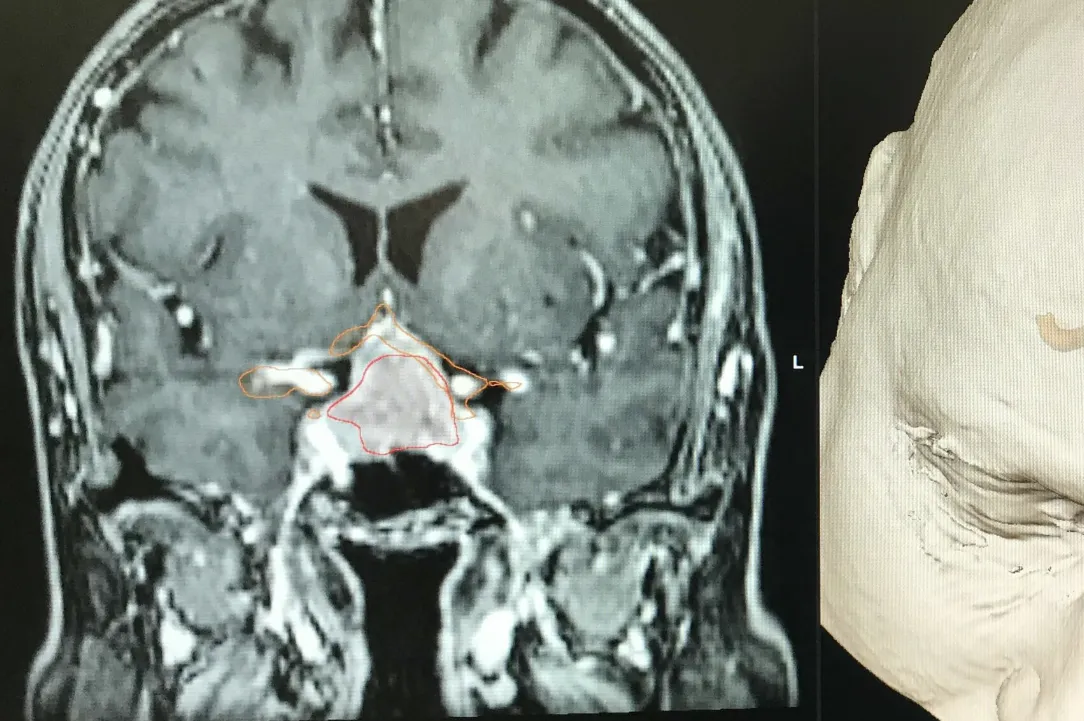

Les adénomes hypophysaires sont majoritairement des tumeurs bégnines qui se développent à partir de la glande hypophysaire.

On peut les catégoriser par leur activité et par leur volume. En effet, ceux-ci peuvent secréter de manière excessive des hormones hypophysaires ou peuvent, par leur volume, comprimer les structures fonctionnelles et, en particulier, le nerf optique et le chiasma.

Les adénomes secrétants sont habituellement découverts de manière plus précoce et sont le plus souvent catégorisés comme des micro-adénomes. Leur traitement est, dans un premier temps, le plus souvent médicamenteux et, en cas d’échappement du traitement médical, peut être chirurgical. Il nécessite dès lors une étroite collaboration entre les endocrinologues et les neurochirurgiens.

Les adénomes non-secrétants sont souvent découverts soit de manière fortuite lors d’une imagerie cérébrale, soit en lien avec leur volume excessif. On parle alors de macroadénomes qui sont responsables de troubles le plus souvent visuels par compression du nerf optique et ou du chiasma. Leur traitement est chirurgical s’ils sont symptomatiques. L’acte chirurgical consiste à l’exérèse de la tumeur via les cavités nasales et le sinus sphénoïdale (voie transnasale, transphénoïdale). L’abord peut se faire sous endoscope ou microscope. La tendance actuelle est d’utiliser la voie endoscopique en étroite collaboration avec l’équipe d’ORL. Dans certaines situations, un traitement combinant l’exérèse chirurgicale et un traitement par radiochirurgie peut être discuté en concertation oncologique multidisciplinaire. Vous retrouverez au sein de notre service de Neurochirurgie du CHIREC, l’ensemble de ces collaborations possibles.